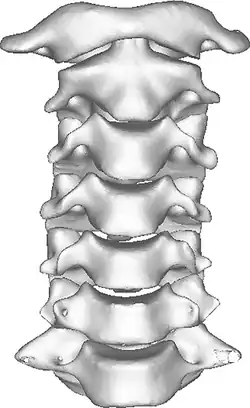

1. Cervical spine x-ray (lateral view)

Once there is an onset of the symptoms in the patient, the patients are screened through cervical-spinal imaging techniques: X-ray, CT, MRI. [1] The scanning technique points out any cervical vertebrae defects and misalignments. (Image 1. and 2.) When cervicocranial syndrome is caused as a result of a genetic disease, then family history and genetic testing aid in making an accurate diagnosis of cervicocranial syndrome.

2. Cervical spine x-ray (odontoid view)